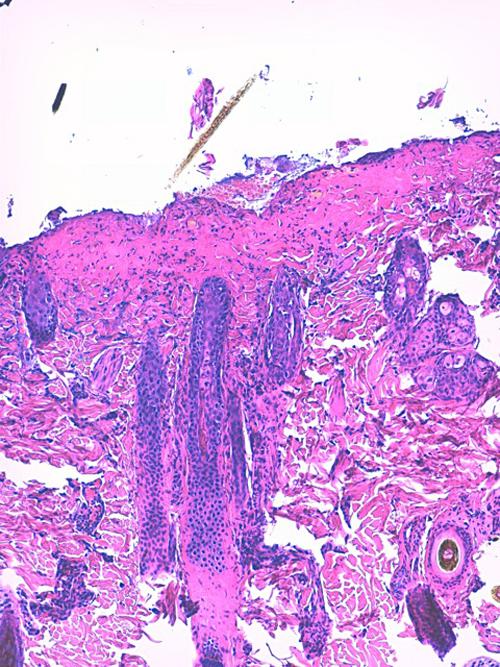

Photo 8 (Hémalun Eosine X 40) : L’épiderme et les infundibula folliculaires

sont hyperplasiques et fortement hyperkératosiques. Le derme montre une inflammation péri-vasculaire.

Légendes de la Photo 8 :

- Double flèche jaune : épiderme (portion non kératinisée)

- Double flèche bleue : couche cornée hyperkératosique

- Double flèche orange : derme

- Étoiles vertes : follicules pileux

- Étoiles rouges : infiltrat dermique périvasculaire